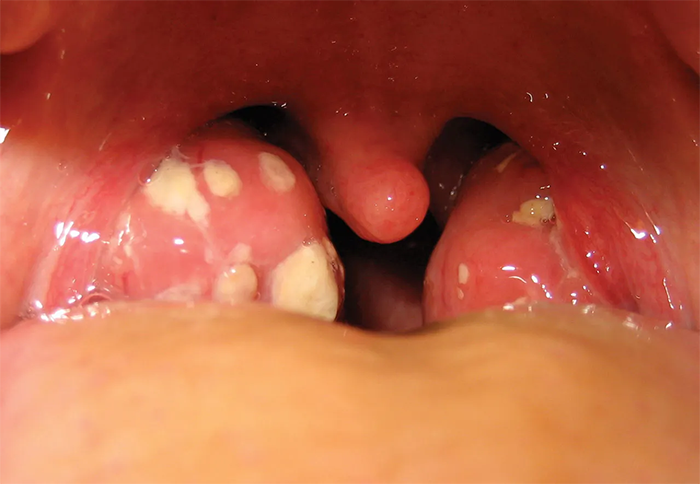

این نوع کیست یک کیسه پر از مایع یا مواد نیمهجامد است که در بافت لوزهها تشکیل میشود. این کیستها غالباً بهصورت کیست احتباسیِ لوزه در اثر انسداد غدد یا مجاری مخاطی/کریپتهای لوزه ایجاد میشوند و معمولاً رشد آهسته دارند.

- کیست احتباسی لوزه (Tonsillar Retention Cyst): شایعترین نوع کیست لوزه. وقتی مجاری ترشحی کوچک یا کریپتهای لوزه مسدود میشوند، مایع یا ترشحات در یک کیسه محصور جمع میشود. معمولاً کوچک، با رشد آهسته، بیعلامت و بهصورت برجستگی نرم یا شفاف روی لوزه دیده میشود و به دلیل انسداد بهدنبال التهاب یا تورم مخاط لوزه ایجاد میشوند.

- کیست لنفواپیتلیال لوزه (Tonsillar Lymphoepithelial Cyst): ضایعهای خوشخیم که از بقایای اپیتلیوم در بافت لنفوئیدی لوزه تشکیل میشود. این کیستها پر از کراتین و مواد سفیدرنگاند. نادر هستند و معمولاً کوچک (کمتر از ۱ سانتیمتر)، اغلب بیعلامت، گاهی با درد یا ناراحتی خفیف همراه هستند.

متاسفانه مواردی مثل سنگ لوزه (Tonsillolith)، آبسه دورلوزه (Peritonsillar abscess) و تومورهای خوشخیم/بدخیم، را کیست معرفی میکنند درحالی که این چنین نیست و توده یا بافت هستند.

کیستهای لوزه در بیشتر موارد بیخطر و غیرسرطانی هستند و بسیاری از افراد بدون اینکه متوجه شوند، سالها با این کیستهای کوچک زندگی میکنند. با این حال، زمانی که این کیستها رشد کنند یا دچار عفونت شوند، میتوانند مشکلاتی مانند احساس گیرکردن چیزی در گلو، ناراحتی هنگام بلع، تنفس دشوار یا حتی بوی نامطبوع دهان به وجود بیاورند. تشخیص دقیق این کیستها اهمیت بسیار زیادی دارد، زیرا گاهی با آبسه یا سنگ لوزه اشتباه گرفته میشوند. درواقع تودهٔ سفید/زرد روی لوزه اغلب سنگ لوزه یا ترشحات تونسیلیت است و آبسهٔ دورلوزه هم تودهمانند دیده میشود؛ اینها کیست نیستند و درمان متفاوتی دارند.